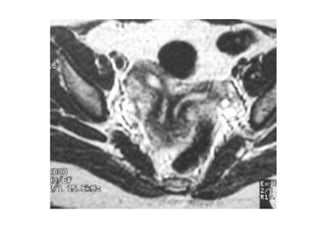

T2-weighted MR image shows a large,

heterogeneous tumor distending the

endometrial canal (arrows).